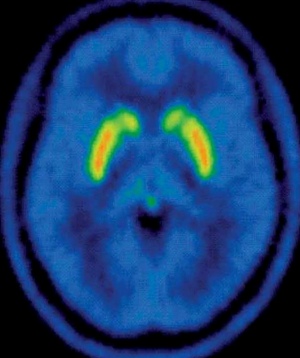

Scientists used molecular imaging to visualize changes in the brains of heavy marijuana smokers versus non-smokers and found that abuse of the drug led to a decreased number of cannabinoid CB1 receptors, which are involved in not just pleasure, appetite and pain tolerance but a host of other psychological and physiological functions of the body.

"Addictions are a major medical and socioeconomic problem. Unfortunately, we do not fully understand the neurobiological mechanisms involved in addiction. With this study, we were able to show for the first time that people who abuse cannabis have abnormalities of the cannabinoid receptors in the brain.

This information may prove critical for the development of novel treatments for cannabis abuse. Furthermore, this research shows that the decreased receptors in people who abuse cannabis return to normal when they stop smoking the drug."

[Jussi Hirvonen, MD, PhD, lead author of the collaborative study between the National Institute of Mental Health and National Institute on Drug Abuse, Bethesda, Md.]

Cannabinoid CF1 receptors disappear with chronic cannabis use: return with abstinence

According to the National Institute on Drug Abuse, marijuana is the number-one illicit drug of choice in America. The psychoactive chemical in marijuana, or cannabis, is delta-9-tetrahydrocannabinol (THC), which binds to numerous cannabinoid receptors (CB1) in the brain and throughout the body when smoked or ingested, producing a distinctive high.

Cannabinoid receptors in the brain influence a range of mental states and actions, including pleasure, concentration, perception of time and memory, sensory perception, and coordination of movement. There are also cannabinoid receptors throughout the body involved in a wide range of functions of the digestive, cardiovascular, respiratory and other systems of the body. Currently two subtypes of cannabinoid receptors are known, CB1 and CB2, the former being involved mostly in functions of the central nervous system and the latter more in functions of the immune system and in stem cells of the circulatory system.

For this study, researchers recruited 30 chronic daily cannabis smokers who were then monitored at a closed inpatient facility for approximately four weeks. The subjects were imaged using positron emission tomography (PET), which provides information about physiological processes in the body. Subjects were injected with a radioligand, 18F-FMPEP-d2, which is a combination of a radioactive fluorine isotope and a neurotransmitter analog that binds with CB1 brain receptors.

Results of the study show that receptor number was decreased about 20 percent in brains of cannabis smokers when compared to healthy control subjects with limited exposure to cannabis during their lifetime.

These changes were found to have a correlation with the number of years subjects had smoked. Of the original 30 cannabis smokers, 14 of the subjects underwent a second PET scan after about a month of abstinence. There was a marked increase in receptor activity in those areas that had been decreased at the outset of the study, an indication that while chronic cannabis smoking causes downregulation of CB1 receptors, the damage is reversible with abstinence.

Information gleaned from this and future studies may help other research exploring the role of PET imaging of CB1 receptors -- not just for drug use, but also for a range of human diseases, including metabolic disease and cancer [7].